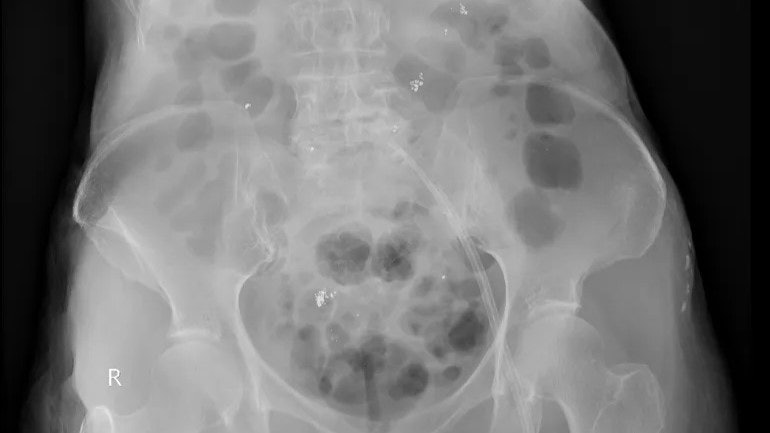

腹平片可以看到患者消化道內殘留大量汞。(南方都市報)